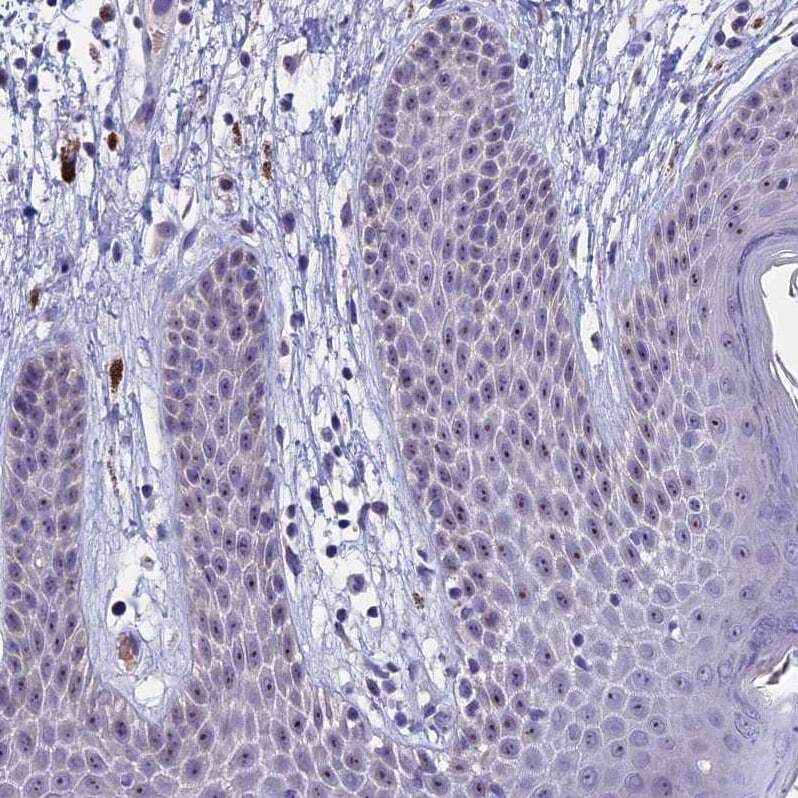

- Submitted by

- Invitrogen Antibodies (provider)

- Main image

- Experimental details

- Immunohistochemical analysis of KNOP1 in human skin using KNOP1 Polyclonal Antibody (Product # PA5-59418) shows strong positivity in nucleoli in squamous epithelial cells.